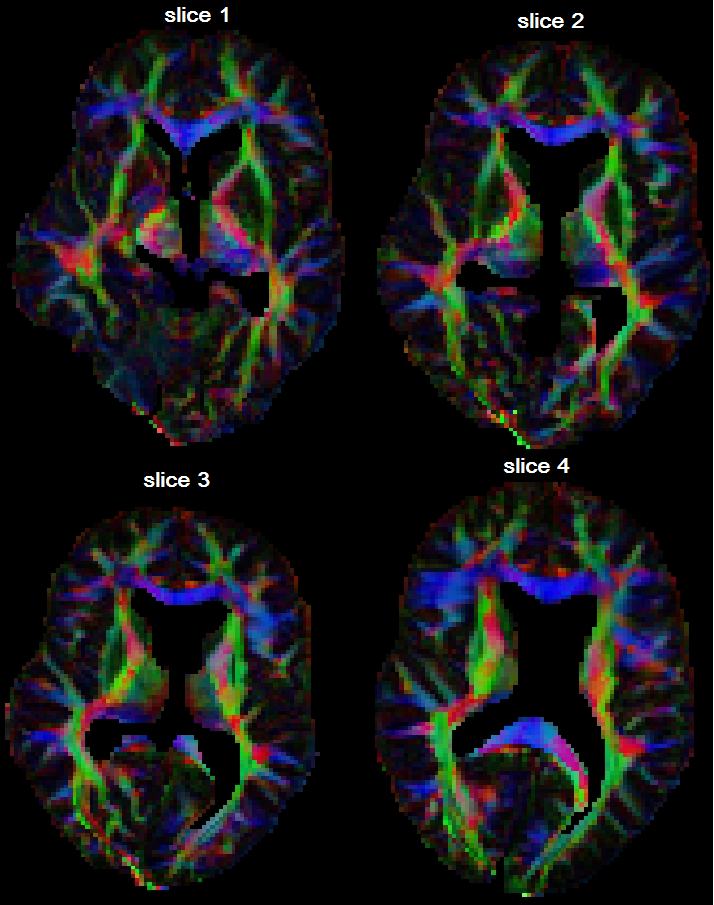

Diffusivity profiles

Fig. 8 shows the diffusivity profiles based on the posterior estimates of the tensors at all voxels in a region of interest. For each direction and spatial location , we plot the point , where is the posterior expectation of the diffusivity. In order to observe the differences between 2nd and 4th order tensor models, in Fig. 9 we zoom into the ROI (a) and (b), and see that the 4th order tensor model captures the fiber-crossings which the 2nd order model cannot capture. At the fiber-crossing locations, under the 2nd-order model the two largest eigenvalues of the estimated tensor have similar sizes, with a donut-shaped diffusivity profile.

Bayesian regularization

In Fig. 10 we compare diffusivity profiles from a region of interest without and with regularization, under the 4th order tensor model.

With regularization, the differences in shape and direction between neighbouring tensors get smoothed. This also

implies noise reduction: the tensor information from data corrupted by artefacts is corrected by the information from the neighbours.

For the 2nd-order tensor model, the regularization effect in the same region was not that evident.